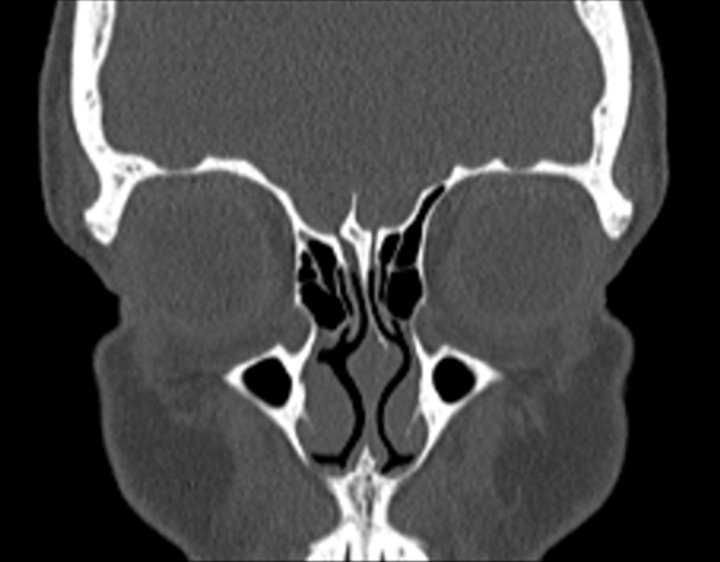

003